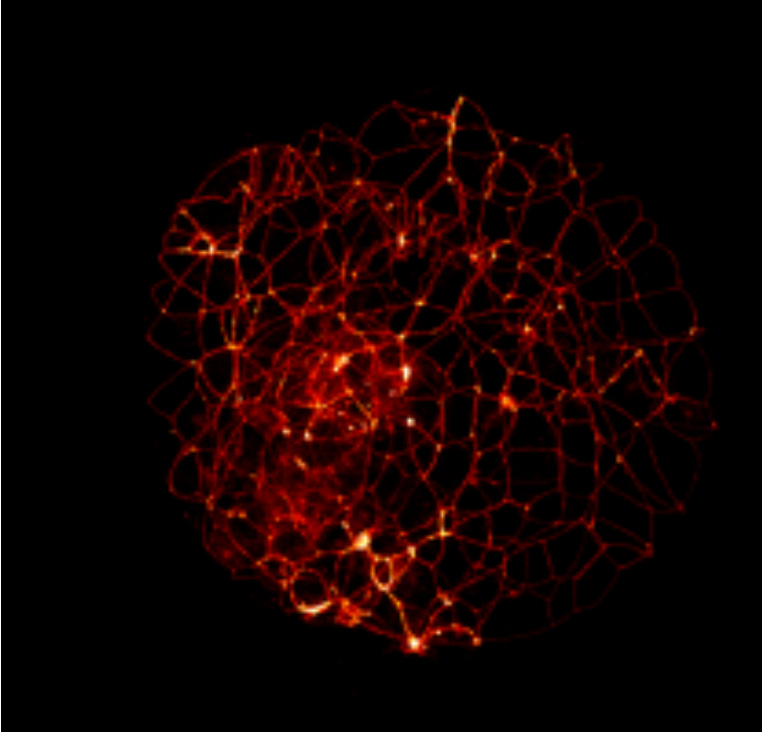

Figure 4. A similar blastocyst-stage embryo is shown after staining for a muscle protein known as actin. The linear pattern shown defines each of the cell boundaries that make up the outer cells of the trophectoderm that will go on to form the placenta.